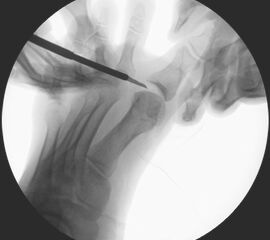

• Intraoperatives Röntgen notwendig.

• Bildverstärker.

• Positionierung des Bildwandlers: 90° Winkel zum Os metatarsale I. Benötigt wird die Durchleuchtung des Vorfußes a.p., seitlich und schräg.

Zum Lesen der Bildbeschreibung und zur Vollansicht bitte die Bilder anklicken.